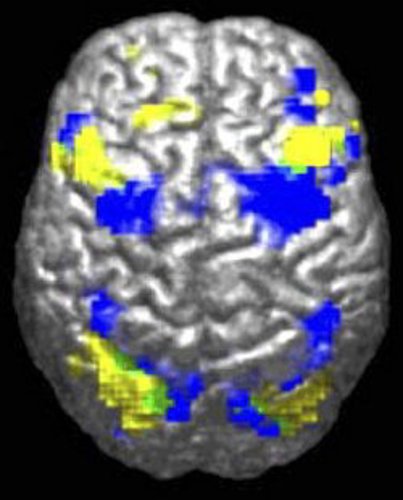

MRI image comparison between people with ASD and people without

When doing a certain task, people with ASD use areas of their brain (yellow) that are different from people without ASD (blue).